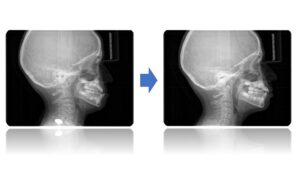

La Classe III Squelettiques

Les classes III squelettiques sont l’expression d’une orientation pathologique du plan occlusal et de la croissance faciale.

L’orthodontie systémique permet d’appréhender cette pathologie par l’analyse des latéralités mandibulaires.

Le traitement qui en découle est donc fonctionnel et stable car il permet non pas seulement une protraction du maxillaire mais une réorientation complète de celui-ci. Cette prise en charge permet de retrouver une proprioception maximale du prémaxillaire dans la mastication, gage de stabilité à long terme.